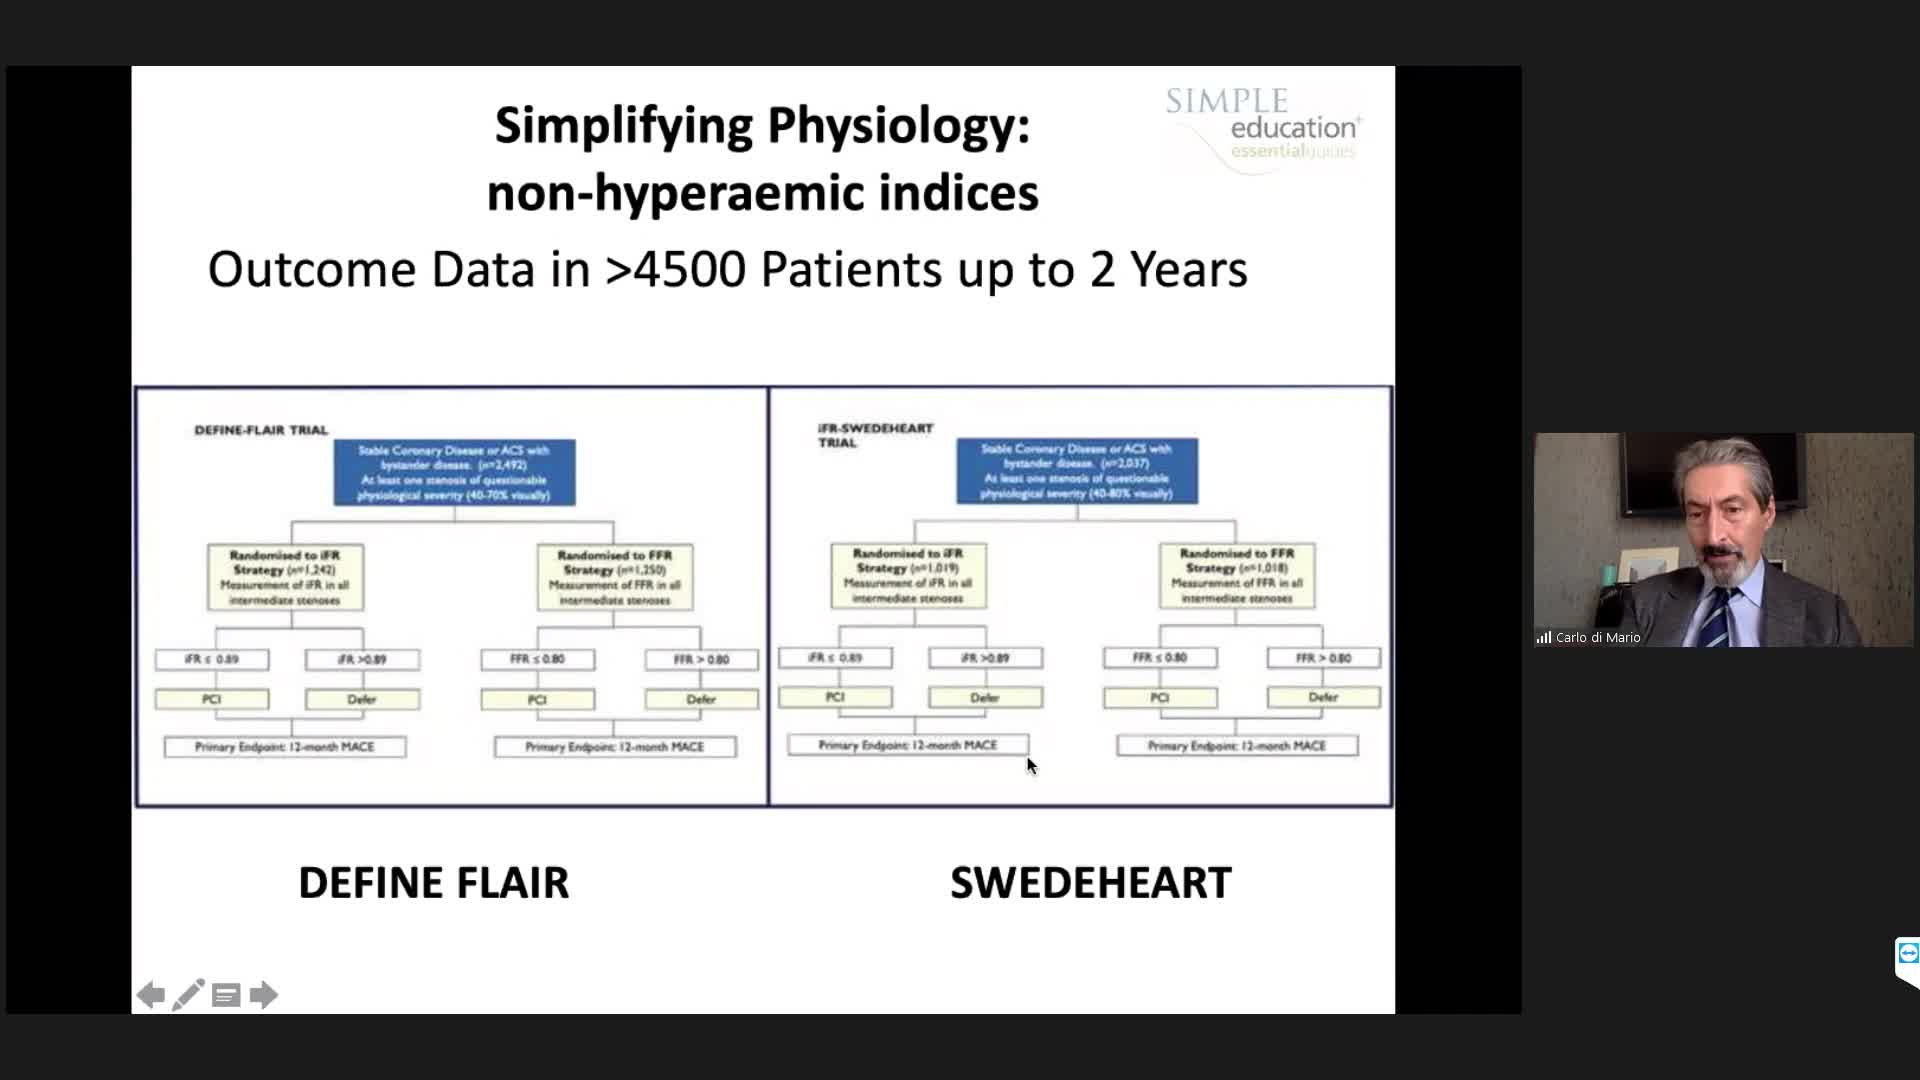

iFR or FFR in the LAD. What does the clinical outcome data tell us? - Dr Sayan Sen

20 year overview of clinical trial data to support the use of coronary physiology in revascularisation decision-making